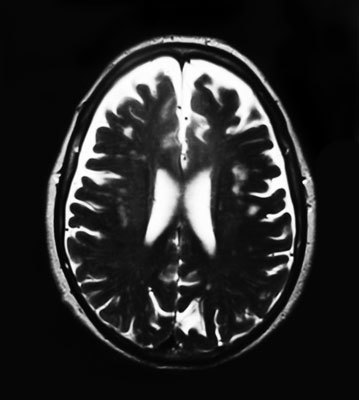

Периодически проходить сканирование очень полезно. Во-первых, потому, что сразу можно увидеть состояние мозга, а во-вторых, подумать о рекомендациях по улучшению образа жизни. Давайте поговорим о распространенном и эффективном методе магнитно-резонансной томографии (МРТ) и некоторых других.

При использовании МРТ пациента помещают внутрь специального устройства и получают изображение нужной области тела. Принцип работы устройства состоит во взаимодействии электромагнитного поля с атомами водорода в организме человека. В результате можно получить подробные изображения структур мозга, а с помощью компьютерной томографии (КТ) – и среза его тканей. К сожалению, этот метод дает не такую подробную картину, как МРТ. Можно также обследовать состояние сосудов мозга с помощью магнитно-резонансной ангиографии (МРА).

Основная цель прохождения МРТ-обследования – обнаружение очагов инсульта, ранних стадий атеросклероза и других заболеваний. Дело в том, что невозможность подобрать нужные слова, неспособность долго размышлять и прочее могут быть вызваны не только нездоровым образом жизни.

МРТ-снимок мозга девушки, которая жалуется на периодические головокружения. Кроме того, она не может сразу подобрать нужные слова. В правой лобной доле (если смотреть на фото так, как есть, – то слева) видна лимфатическая мальформация.